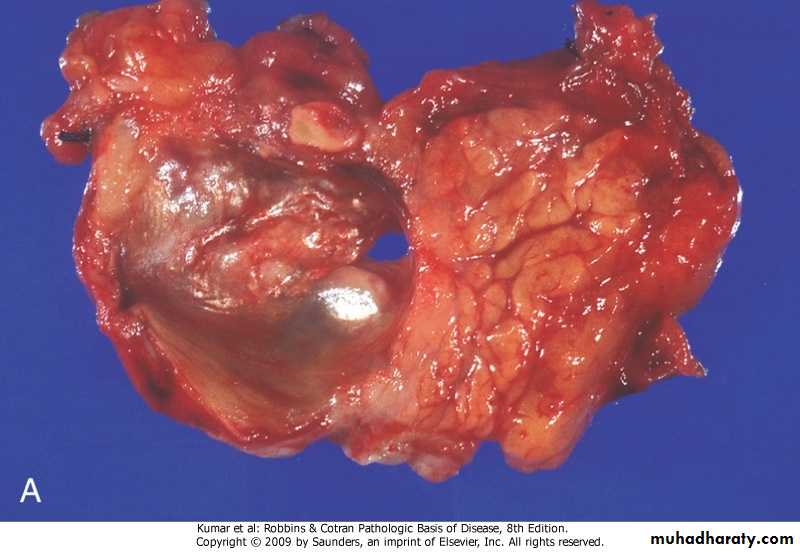

Morphology

Gross :Enlargement of liver.

Areas of necrosis and hemorrhage .

light brown, yellowish-white or gray in color.

Three patterns.

A. Unifocal (usually large): Tumor appears as large circumscribed single mass .B. Multifocal: This multiple nodules of variable size widely distributed.

C. Diffusely infiltrative: large part of the liver or sometimes entire liver infiltrated by homogeneous indistinct tumor nodules.

Microscopy :

HCC range from well-differentiated, moderately differentiated, and undifferentiated (pleomorphic) forms.Hepatocellular carcinoma